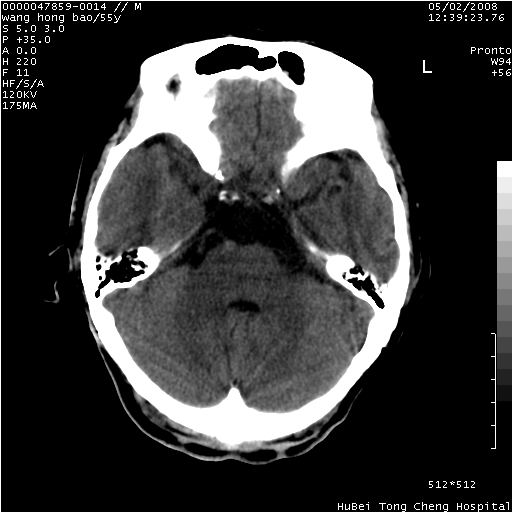

以下是引用dyqct在2008-5-3 23:36:00的发言:[br]桥前池区可疑蛛网膜囊肿。其它未见明显异常。建议做mri。

以下是引用qiushi在2008-5-4 10:10:00的发言:[br]鞍上池前缘突出影为双侧额叶直回;箭头所指为双侧正常之人字缝.[br]桥前池区可疑表皮样囊肿或蛛网膜囊肿,必要时mri

以下是引用zjzjr在2008-5-4 14:50:00的发言:[br]桥前池区可疑蛛网膜囊肿。其它未见明显异常。建议做mri。